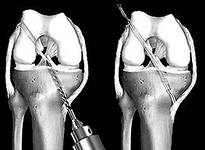

Если диагностируют нестабильность сустава, причиной которого стал разрыв связок (одной или нескольких), то поврежденные структуры восстанавливают, используя сухожилия колена. Хирург формирует каналы (в соответствии с направлением связки) в берцовой и бедренной кости, по которым проводит трансплантат (рис 5). Закрепляют трансплантаты винтами (они могут быть металлическими или саморассасывающимися), «пуговицами», пластинами, штифтами, которые оставляют в суставе навсегда (рис 6,7). После операции ногу на месяц фиксируют при помощи ортеза. Когда боль утихнет, что происходит на второй-третий день, назначают занятия ЛФК.